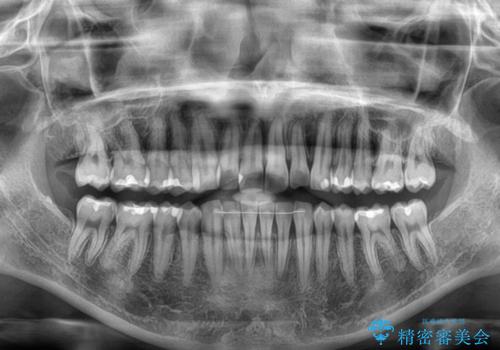

- 上下前歯の重なりを気にして来院された患者様です。

安価なインビザラインパッケージを用いての治療を希望されており、デコボコの程度が中等度であったため、インビザライン・モデレートを用いて矯正治療を行うこととしました。

インビザライン・モデレートは、製作できるアライナーの枚数に制限があるため、移動可能な量に限りがあるものの、インビザライン・ライトよりも枚数が多いため、幅広い症例に対応可能です。